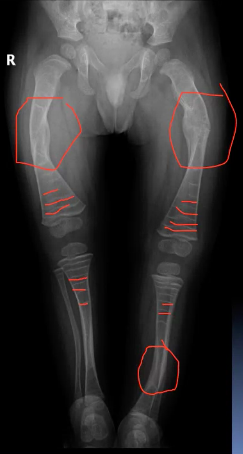

A mother brought her six-week old daughter to the ED. The child had become very irritable after the mother had accidentally twisted the infant’s right leg whilst changing her nappy.

The child was irritable and became distressed when her right leg was examined.

What abnormalities can you see in the X-ray of this child’s lower limb bones?

Can you explain the abnormal appearance?